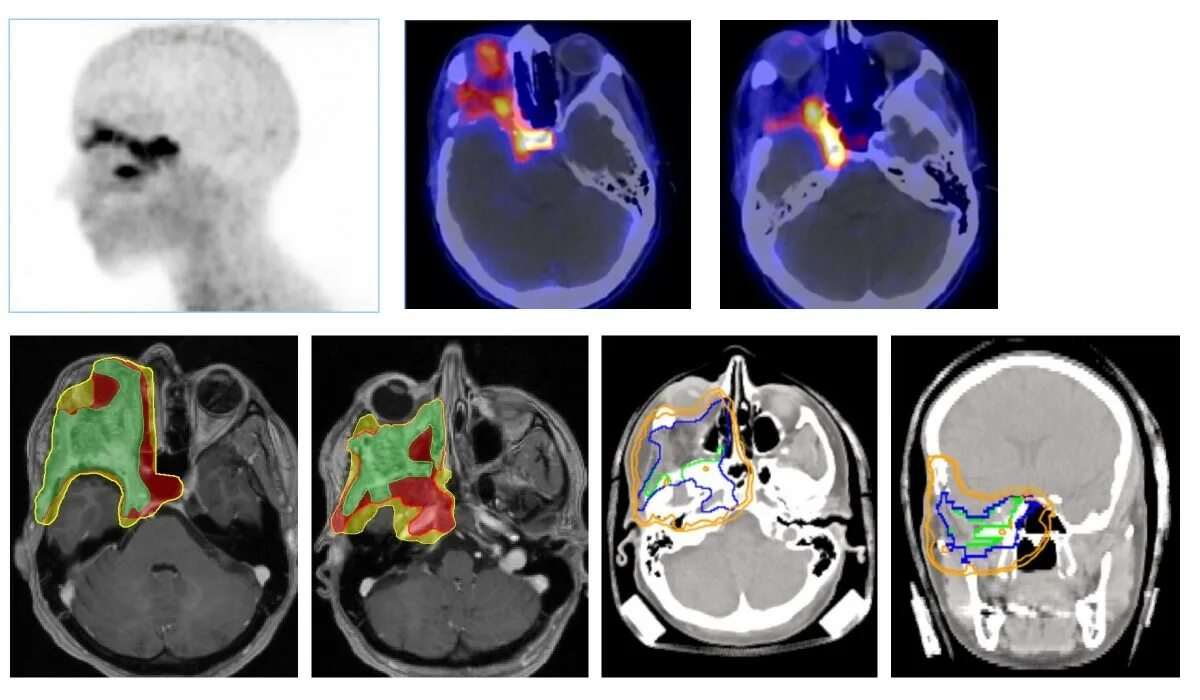

Чем отличается кт от мрт головного